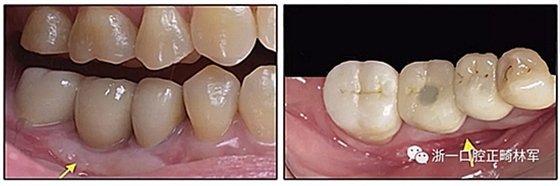

圖11.38個月時上頜與治療前的對比

圖15.A,去除固定裝置一個月后,下頜左側第二前磨牙復發(fā),移動到種植體愈合的部位; B,B-0表示開始再治療,通過鏈圈和推簧的矯正復發(fā); C,B-9是治療結束后3個月回訪時下頜弓的咬合面觀,這是再治療階段的9個月。下頜左側第二前磨牙和第三磨牙的頰面粘合一個固定保持器,以防止復發(fā)。